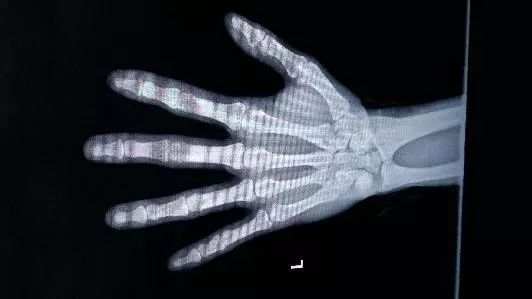

人体骨格发育过程中 ,继发骨化中心的出现,完全骨化及骨干闭合是依一定时间展序进行的,根据这种规律而推断的年龄,称为骨龄。如无影响骨骼发育的疾病存在,这种推断有相当的准确性。骨龄是借助于骨骼在X光摄像中的特定图像来确定。在了解人的骨龄情况时,通常要拍摄人六大关节、左手的X光片,医生通过X光片视察左手掌指骨、腕骨及桡尺骨下端的骨化中心的发育程度,来确定骨龄。根据骨化点的出现情况与愈合的顺序推断婴儿至青春期者的年龄较为可靠。